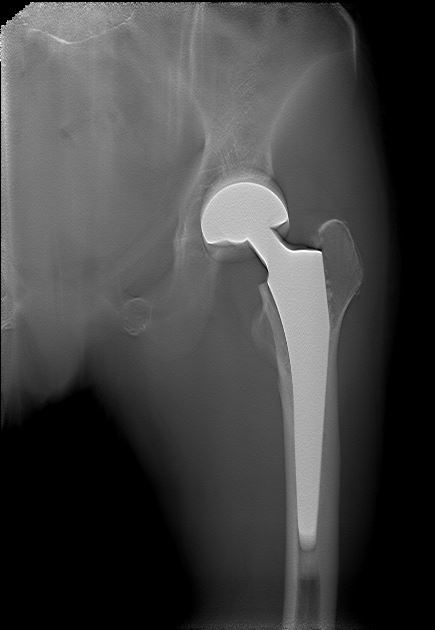

女   83岁

左侧股骨头置换术后

左髋关节正位片

左侧股骨头置换术后复查

容积断层图像可以清晰显示置换的股骨头与髋臼的关系,也可以清晰显示植入物与股骨干之间的嵌合情况,为术后评估提供影像资料。